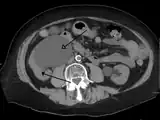

Peripelvic renal cysts may look like hydronephrosis on non-contrast CT (left image). However, CT urography (at right) reveals non-dilated calyces and pelvises.